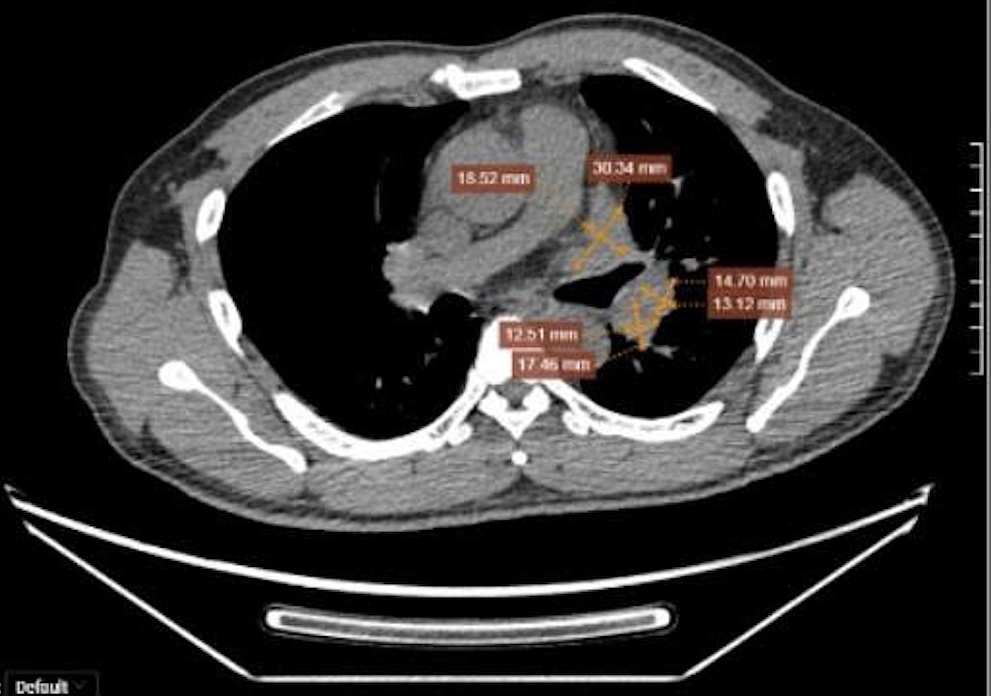

CT and PET/CT scan results for Mr. Truong Van Dung revealed a 58x29 mm tumor in his left lung, which had invaded the adjacent mediastinal pleura, forming a large mass measuring 33x24 mm at the left lung hilum.

Mr. Dung's malignant tumor had invaded and spread to adjacent organs, forming multiple nodes and large masses. Photo: Tam Anh General Hospital